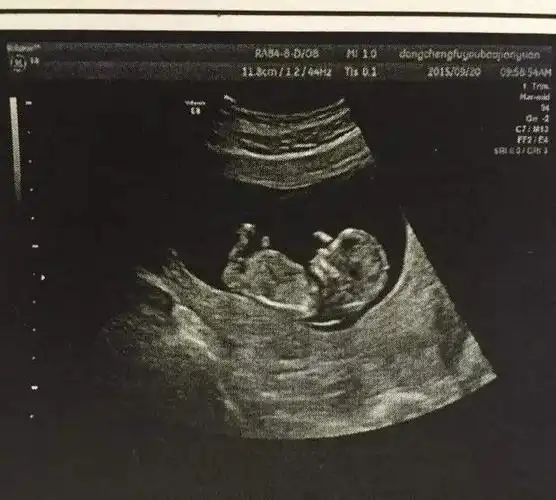

英孕妇做b超惊现歌王杰克逊影像